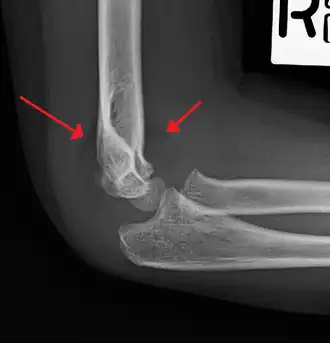

Tear drop sign - Tear drop sign is seen on a normal radiograph, but is disturbed in supracondylar fracture.[8]

Anterior humeral line - It is a line drawn down along the front of the humerus on the lateral view and it should pass through the middle third of the capitulum of the humerus.[9] If it passes through the anterior third of the capitulum, it indicates the posterior displacement of distal fragment.[8]

Fat pad sign/sail sign - A non-displaced fracture can be difficult to identify and a fracture line may not be visible on the X-rays. However, the presence of a joint effusion is helpful in identifying a non-displaced fracture. Bleeding from the fracture expands the joint capsule and is visualized on the lateral view as a darker area anteriorly and posteriorly, and is known as the sail sign.[8]

Coronoid line - A line drawn along the anterior border of the coronoid process of the ulna should touch the anterior part of the lateral condyle of the humerus. If lateral condyle appears posterior to this line, it indicates the posterior displacement of lateral condyle.[8]

Fish-tail sign - The distal fragment is rotated away from the proximal fragment, thus the sharp ends of the proximal fragment looks like a shape of a fish-tail.[8]